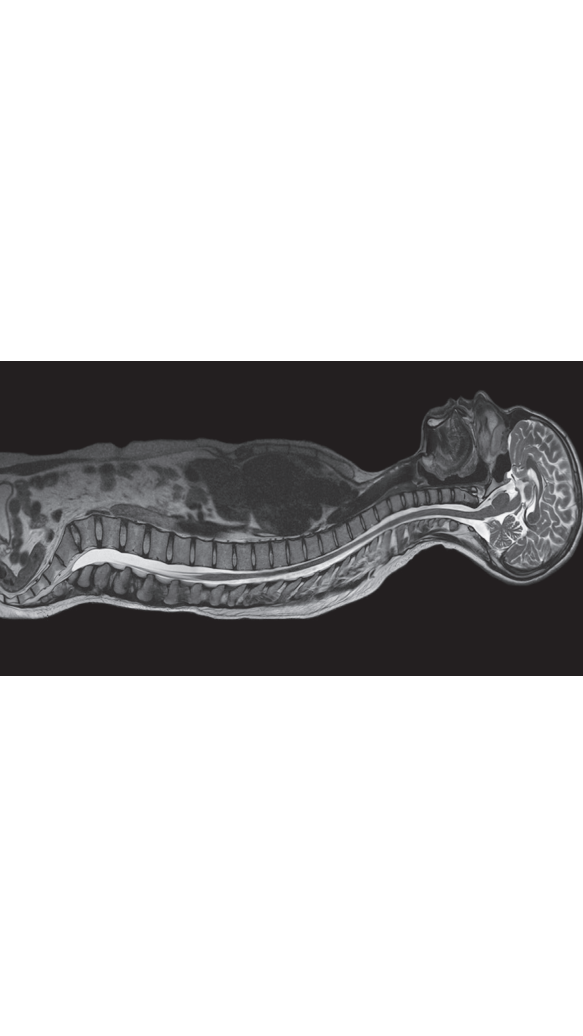

고화질 확산 강조 영상 획득 : 고화질 확산 강조 영상을 이용해 뇌 뿐만 아니라 복부, 척추, 관절 등에서도 확산영상을 얻어 전이성 악성 병변의 판별이 더욱 용이합니다.

수 많은 임상 영역에서 Thin slice 영상촬영 가능 : 머리, 다발성경화증, 경추, 요통, 골반 및 복부질환 등 복잡한 임상 영역에서 Thin slice 영상촬영이 가능하여 선명한 화상 이미지를 얻어 정확한 진단이 가능합니다.